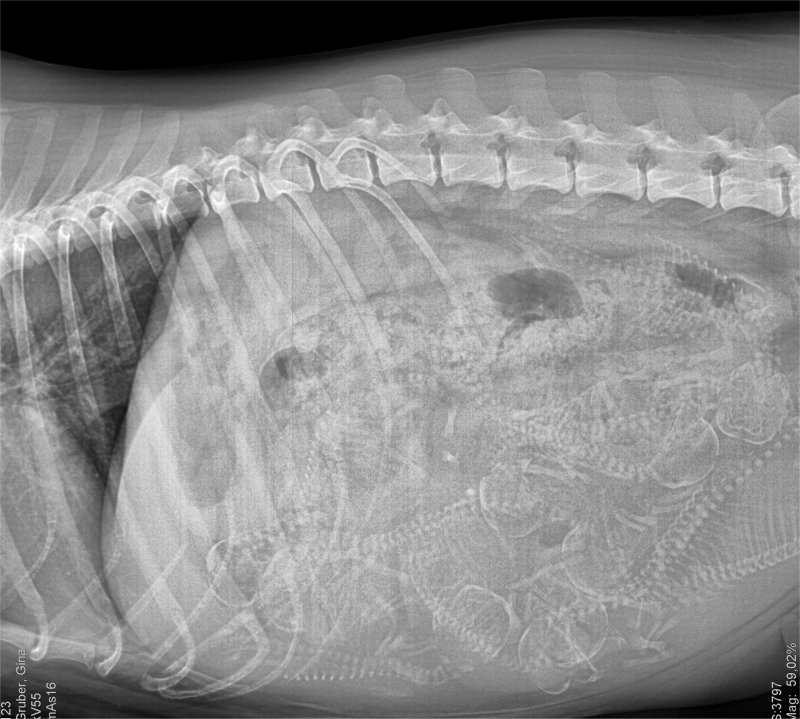

Voraussichtlicher Geburtstermin 19.09.2018

Wir sind schon gewachsen: (Röntgenbild)